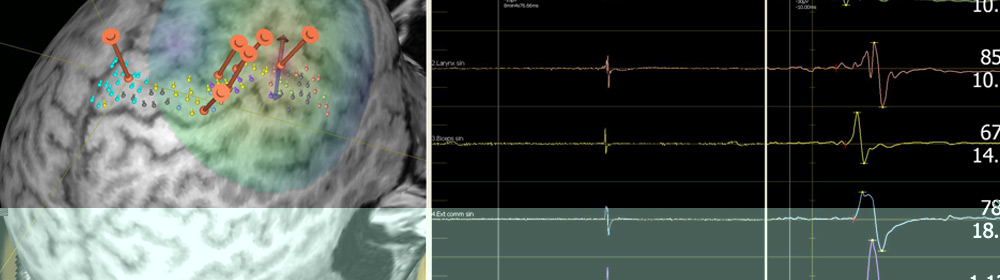

ТМС - современный метод картирования мозга, а также персонифицированной диагностики и лечения заболеваний нервной системы